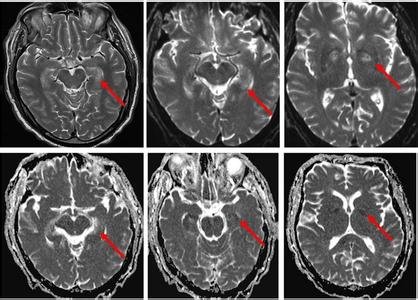

1.3.3 ENs的定义 ENs是脑缺血后出现的胞质嗜酸性及细胞核固缩、碎裂、溶解的神经元。缺血急性期部分ENs的细胞核异常伴胞浆嗜酸性,细胞体由肿胀至萎缩、由圆形至不规则。ENs根据形态学特征分为6种类型见表2:核轻度异常和胞体肿胀(图1C、G、H,箭头);核固缩和胞体不规则萎缩(图1D,箭头);核固缩和胞体极度萎缩(图1E,箭头);核固缩和胞体轻度萎缩(图1H、I,楔形箭头);核碎裂和胞体轻度萎缩(图1I,空白箭头);核溶解和胞体轻度萎缩(图1T、J,箭头)。

首先行HE染色,拍照记录各型ENs,然后脱去HE染色,检测细胞死亡相关因子在各型ENs的表达(表3,图2)。

缺血中心区,核轻度异常和胞体肿胀的ENs表达calcium(64.5±9.4)%、μ-calpain(46.5±8.3)%、GRP 78(78.8±14.4)%、ubiquitin(75.7±11.6)%等细胞死亡相关因子。胞体不规则萎缩的ENs中calcium(91.4±7.2)%、μ-calpain(88.9±10.7)%的表达增高。胞体极度萎缩的ENs中calcium、TUNEL染色的阳性率分别为(73.8±10.2)%、(85.4±7.5)%,而胞体不规则萎缩与胞体极度萎缩的ENs中活化型caspase 3均呈阴性。

周边区,核轻度异常和胞体肿胀的ENs中也表达calcium(60.5±10.7%、GRP78(75.8±12.6%、ubiquitin(70.7±12.7)%等细胞死亡相关因子,但μ-calpain(8.1±4.4)%呈阴性。核固缩、核碎裂的ENs中钙染色的阳性率分别为(64.6±13.1)%、(47.9±13.4)%;TUNEL染色在两种ENs中的阳性率分别为(69.4±8.5)%、(71.6±9.4)%;而caspase 3(2.6±1.8)%、(4.5±3.5)%和μ-calpain(4.5±3.5)%、(3.6±3.3)%在两种ENs中始终呈阴性。